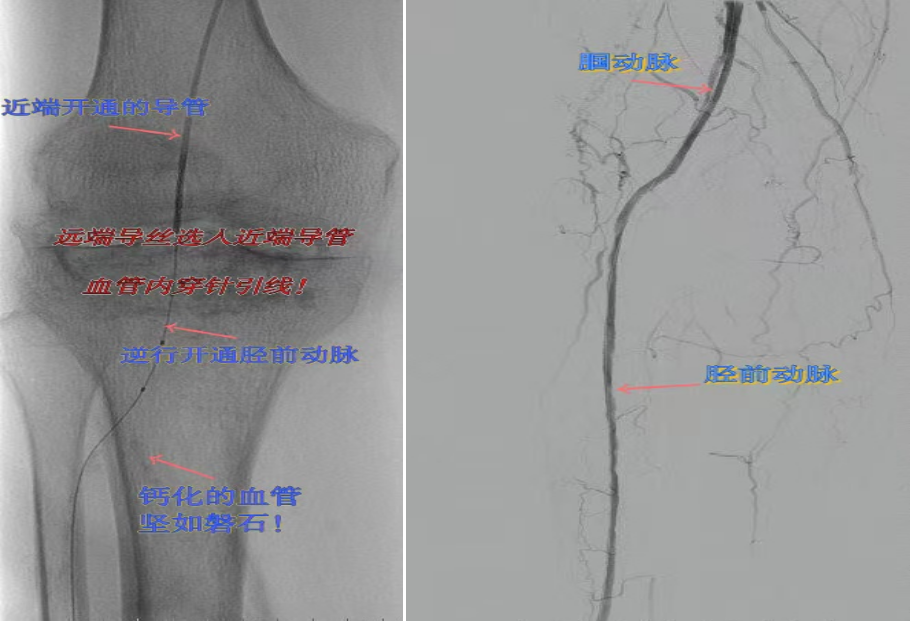

67歲女性患者,多年糖尿病、冠心病史,因右足潰爛伴涼麻疼痛長(zhǎng)達(dá)2年就診,此前曾接受外院介入術(shù)后血管再度閉塞。此次檢查發(fā)現(xiàn)其股淺動(dòng)脈、腘動(dòng)脈至膝下血管全程閉塞,且伴有嚴(yán)重鈣化。團(tuán)隊(duì)迎難而上,創(chuàng)新性經(jīng)足背動(dòng)脈逆向穿刺,耗時(shí)3小時(shí)成功貫通脛前動(dòng)脈。術(shù)后當(dāng)夜患者足部即感回暖,潰爛足趾疼痛顯著緩解。術(shù)后結(jié)合中藥外治(換藥、熏洗、去腐生肌膏外敷)加速創(chuàng)面愈合。該患者已于出院,院外換藥治療。

影像檢查:股淺動(dòng)脈、腘動(dòng)脈至膝下血管全程閉塞伴嚴(yán)重鈣化。

兩例患者共同凸顯三大高難度治療挑戰(zhàn):1.患者高齡且基礎(chǔ)病復(fù)雜;2.血管全程多節(jié)段閉塞、鈣化程度嚴(yán)重;3.常規(guī)順向開(kāi)通路徑已被完全阻斷。團(tuán)隊(duì)果斷采用遠(yuǎn)端逆行穿刺技術(shù),在纖細(xì)的足踝部血管建立治療通道,實(shí)現(xiàn)“逆向破冰”。